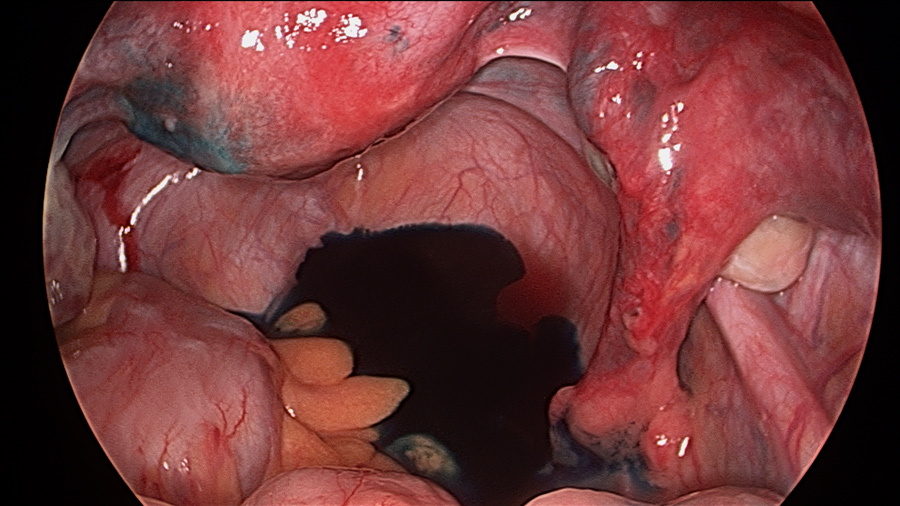

Laparoscopy and Dye Test

Laparoscopy is generally regarded as being the gold standard for the assessment of pelvic health and for checking the patency of the fallopian tubes. This is part of the routine assessment of infertility. Tubal damage is the cause of infertility in about 15% of infertile couples.